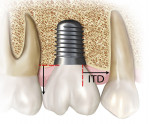

Only implants that were placed adjacent to at least one natural tooth were included. Data collected encompassed the following categories: (1) horizontal distance from the abutment/platform connection to the adjacent tooth root as measured at the alveolar crest; for platform-switched implants the distance from the outer aspect of the abutment connection was used as the measuring point instead of the outer diameter of the implant (Figure 1); (2) vertical distance from the apical portion of the prosthetic contact area to the implant platform (as measured radiographically); and (3) presence or absence of previous restorations on adjacent proximal tooth surface.